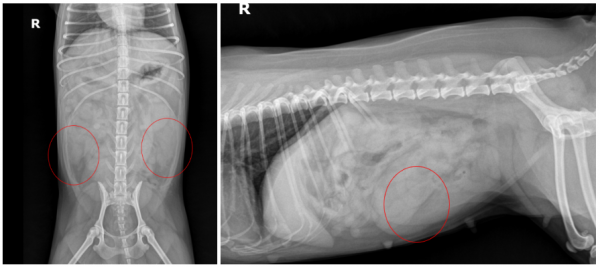

더 정확한 상태를 확인하기 위해 영상 검사를 진행했습니다.

먼저 방사선 검사(X-ray)에서

➡ 복강 내에 연부조직 밀도의 원통형 구조물이 확인되었으며,

확장된 자궁으로 의심되는 소견이었습니다.